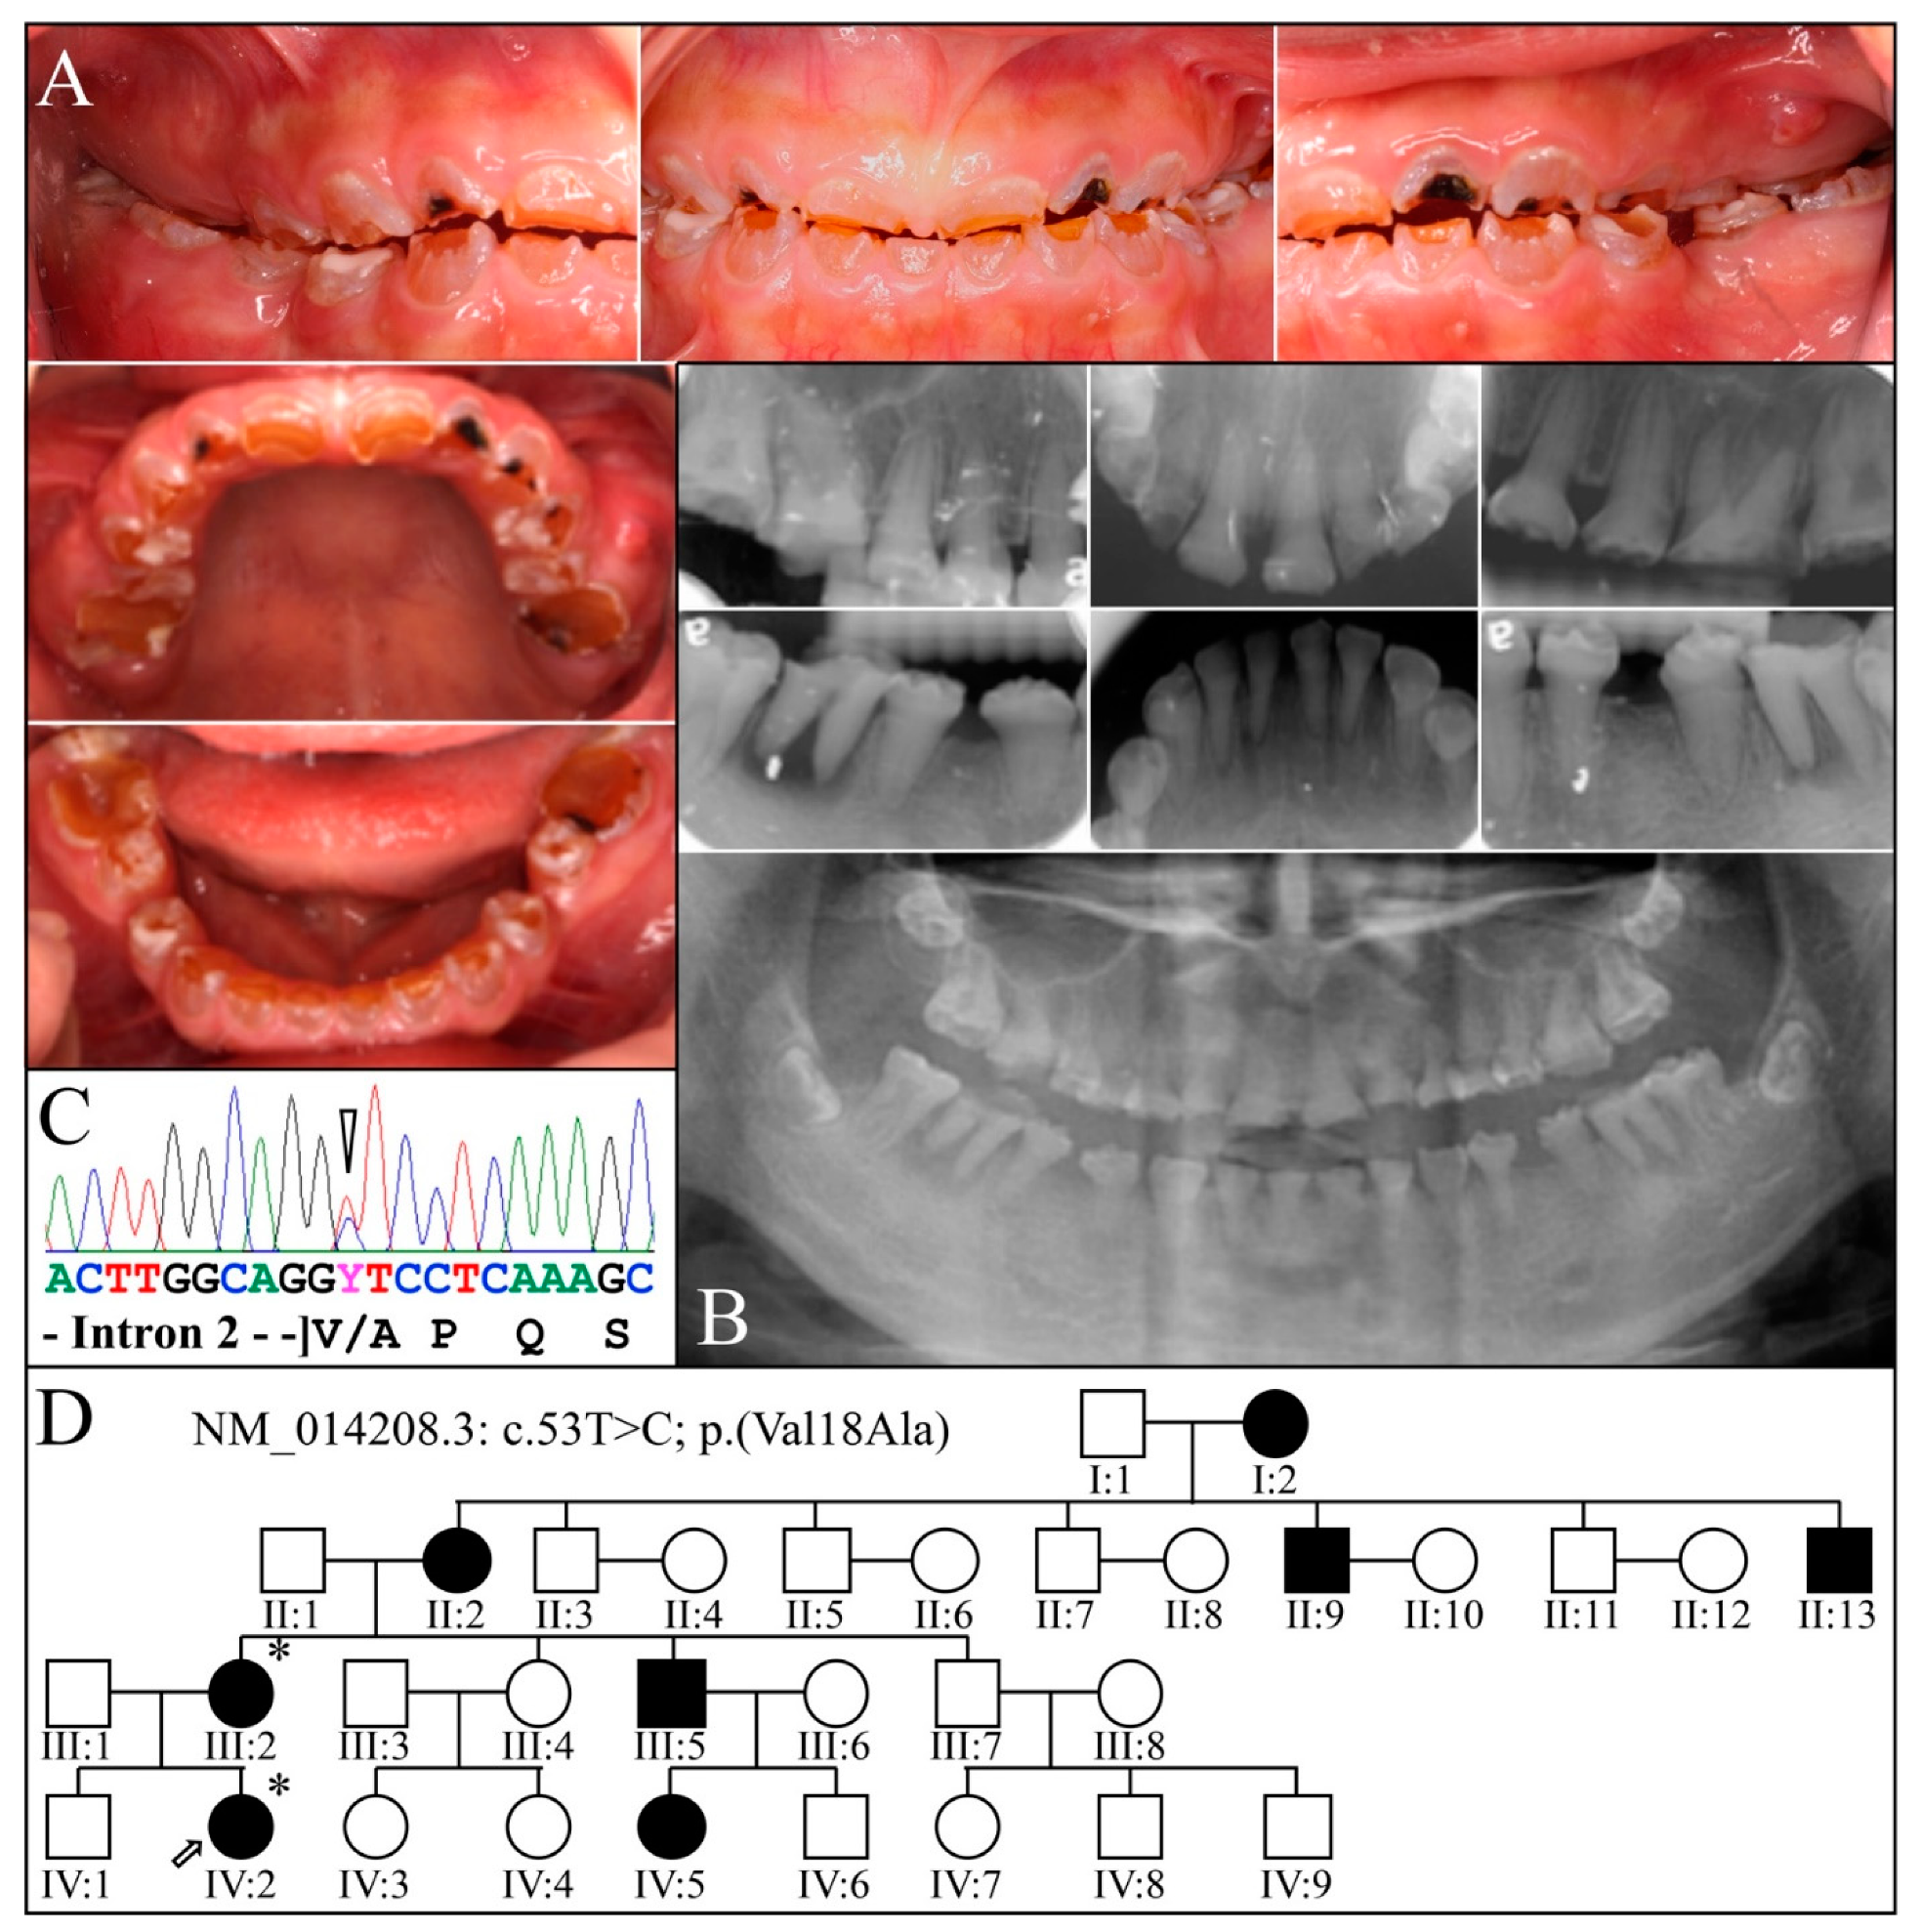

3.2. Four Families with DGI-III: 5′ DSPP Mutations

| 15 | Exon 3 | g.8578T>C | c.53T>C | p.(Val18Ala) | Family 3 |

| 11 | Intron 2 | g.8576G>A | c.52-1G>A | p.(?) | Family 2, [69] |

| 3 | Illumina HiSeq 2500 (WES) | NG_011595.1:g.8578T>C; NM_014208.3:c.53T>C; NP_055023.2:p.(Val18Ala) | Missense | III:2, affected mother: 285.78× IV:2, affected child: 189.42× |

| 2 | Illumina HiSeq 2500 (WES) | NG_011595.1:g.8576G>A; NM_014208.3:c.52-1G>A | Splice Acceptor | IV:2, affected 2nd child: 177.72× |